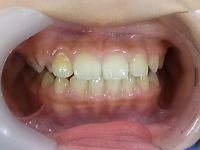

今回の症例はムー・トレーナー<t4k>や

私独自の方法によって改善した症例です。

治療前 治療後